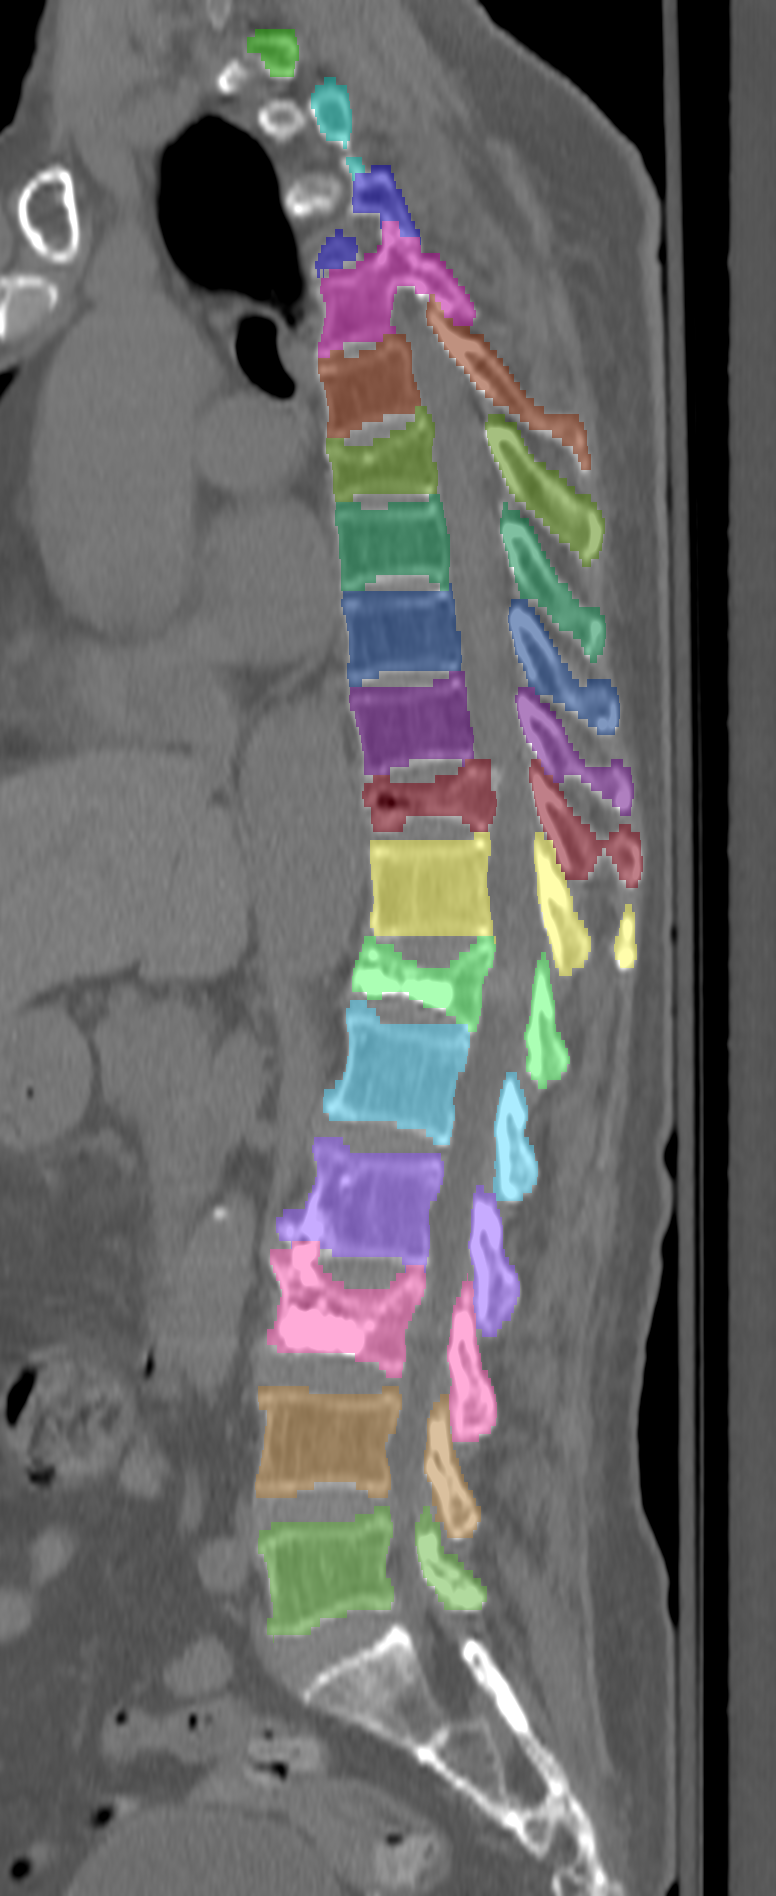

Normalized CT images and reference segmentations of thoracic and lumbar vertebrae from the CSI 2014 workshop

Description

This is the dataset of the vertebra segmentation challenge of the CSI 2014 workshop that was held in conjunction with MICCAI 2014.

- Vertebrae have been anatomically labeled (8 = T1, 9 = T2, ..., 24 = L5)

- Because not always all visible vertebrae were segmented in the original data, only segmentations of the thoracic and lumbar vertebrae have been retained

The resolution and segmentation quality of the diseased cases (16-20) is quite low.